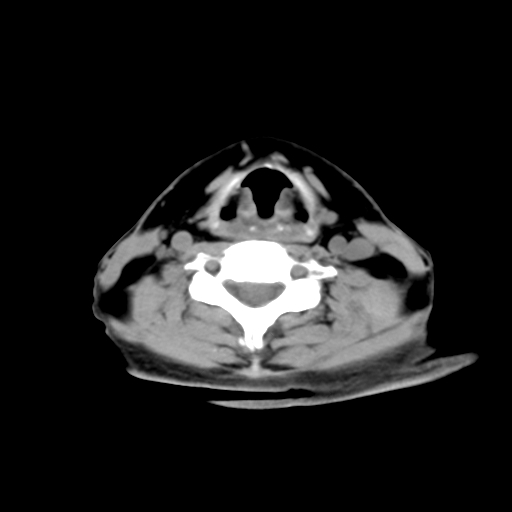

标题: CT24019:男,45岁,发现颈部肿物5个月。 [打印本页]

男,45岁,发现颈部肿物5个月,彩超示:双侧颈部及下颌部软组织增厚。

考虑双侧颈项部良性对称性脂肪增多症。